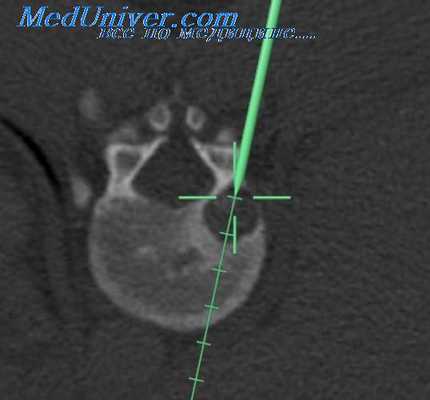

Вмешательство может успешно выполняться как под местной, так и под общей анестезией с обязательным использованием рентгеноскопического контроля. Перед операцией рентгенологически уточняется уровень патологии. После обработки операционного поля 22G иглой, вводимой на расстоянии 1,5-2 см от средней линии на уровне соответствующего межпозвоночного промежутка, рентгенологически уточняется уровень пораженного диска. Игла следует вперед в направлении нижнего края верхней пластины дуги в точку, расположенную между остистым отростком и суставным отростком.

Затем продолжается эндоскопическая диссекция тканей около позвоночника. Сегментарные сосуды (aa.lumbales и vv.lumbales) при необходимости, в зависимости от хода операции, выделяются, клипируются и пересекаются между клипсами. Это позволяет увеличить подвижность брюшной аорты и нижней полой вены, дает возможность подойти к передним и переднебоковым отделам позвонков поясничного отдела. После этого этапа визуализируются передняя поверхность межпозвоночного диска и передняя продольная связка. В диск вводится игла Steinmann и рентгенологически уточняется уровень патологии. Затем производится выделение m.psoas major с боковой поверхности позвонков.

Размер кейджа, необходимого для установки, определяется после дискэктомии и измерения образовавшейся полости между позвонками. Установка стабилизирующей системы осуществляется под прямым эндоскопическим контролем. Производится рентгенологическое подтверждение расположения кейджей в межпозвоночном промежутке.